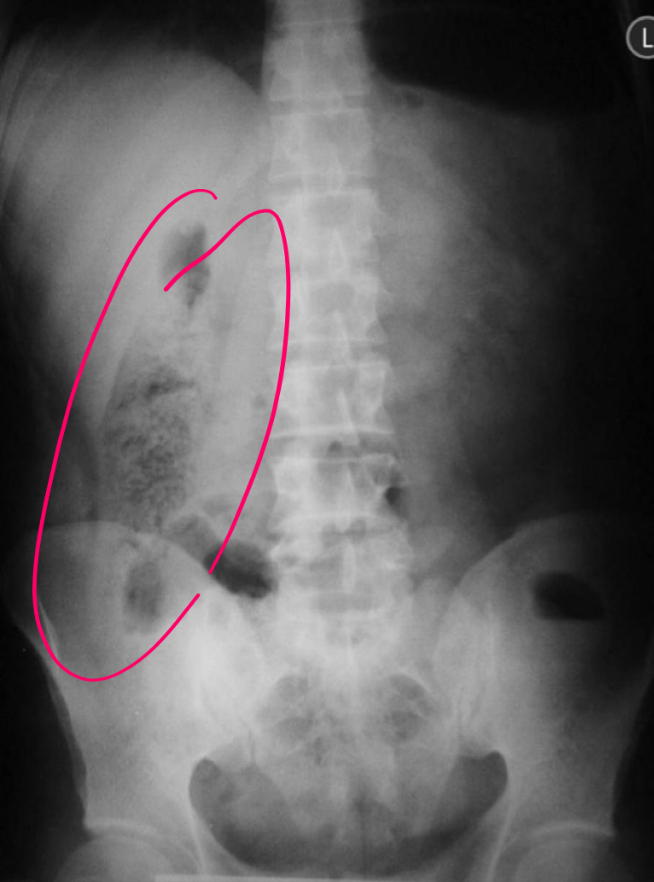

9

que es eso

A

Patron migas de pan: carga fecal en colon ascendente

DATO 2rio apendicitis